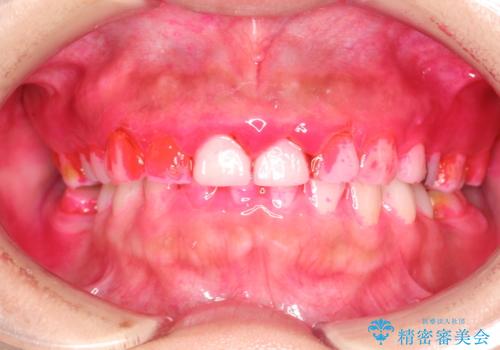

治療途中

かなり久しぶりの歯科医院との事で、全体的に古くからの歯垢・歯石が多く付着していたため、自費クリーニング(PMTC)60分コース・歯周ポケット検査(保険適応)を行いました。